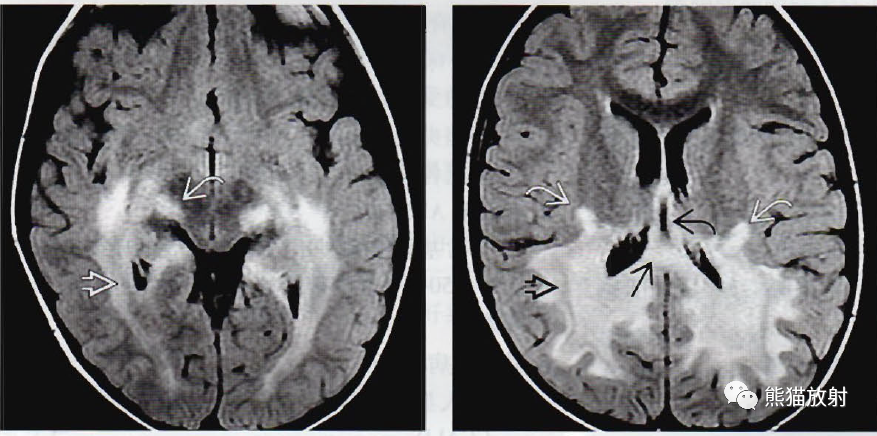

(左)轴位绘图显示多发层状脱髓鞘,分层与3个组织病理学上的分区相对应。外层(弯箭)由活动性病变组成,中间层(空箭)是活动性炎症。注意到中心区(直箭)彻底毁损。

(右) 一位典型的CCALD的青春前期的男孩,轴位T1WI MR显示围绕严重破坏的顶叶白质(弯箭)和胼胝体压部(空箭)的边缘存在显著强化。

(左) 一位大脑完全受累的青春前期的男孩,轴位T2WI MR可分辨外层的活动性炎症(白箭)和最内层白质破坏的“彻底毁损”区(黑箭)。

(右) 另一位患CCALD的有临床症状的青春前期男孩,DTI序列的胼胝体轴位纤维束成像显示穿经胼胝体压部(箭)和胼胝体辐射线枕部的白质纤维束明显缺失。